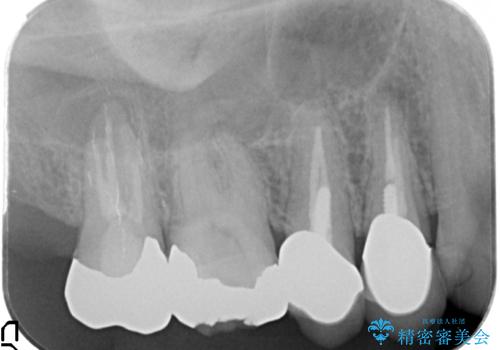

- 歯にものがつまり、以前治療したクラウンの見栄えの悪さの改善を求めて来院されました。

歯ぐきとの境目が、クラウンでしっかりと覆われていないため精密なセラミッククラウンで機能性を回復していきます。

精密なセラミッククラウン製作には、シリコン印象などを用いた精密な型取り、クラウンの製作が大切です。